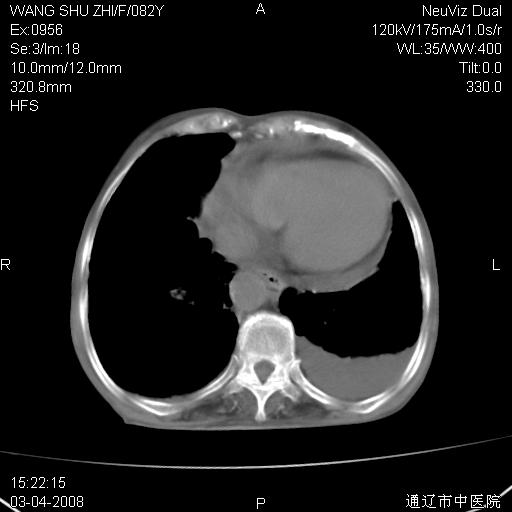

该患者为女性,82岁,既往肺心病、心衰病史。上纵隔影增宽,是否为畸形扩张的血管呢?因该患者年龄太大,又有较严重心脏病,故不适宜做增强检查。

中纵隔肿块最多见是淋巴瘤,而且以hd为多见,呈侵袭性生长,纵隔脂肪间隙消失,再加上心包和双侧胸腔积液,考虑为淋巴瘤(hd)应该说比较准确的。至于说是畸形的血管可能性小,因为畸形血管周围脂肪间隙应该存在。

纵隔淋巴结转移或淋巴瘤;双侧胸腔积液,心包积液。肺窗呢?

病史太简单,年龄太大,首先考虑转移!左侧腋窝亦见肿大淋巴结。

左侧腋窝及纵隔内见多个肿大淋巴结影,左侧少量胸腔积液,心包积液,支持淋巴瘤可能性大,不除外淋巴结转移。